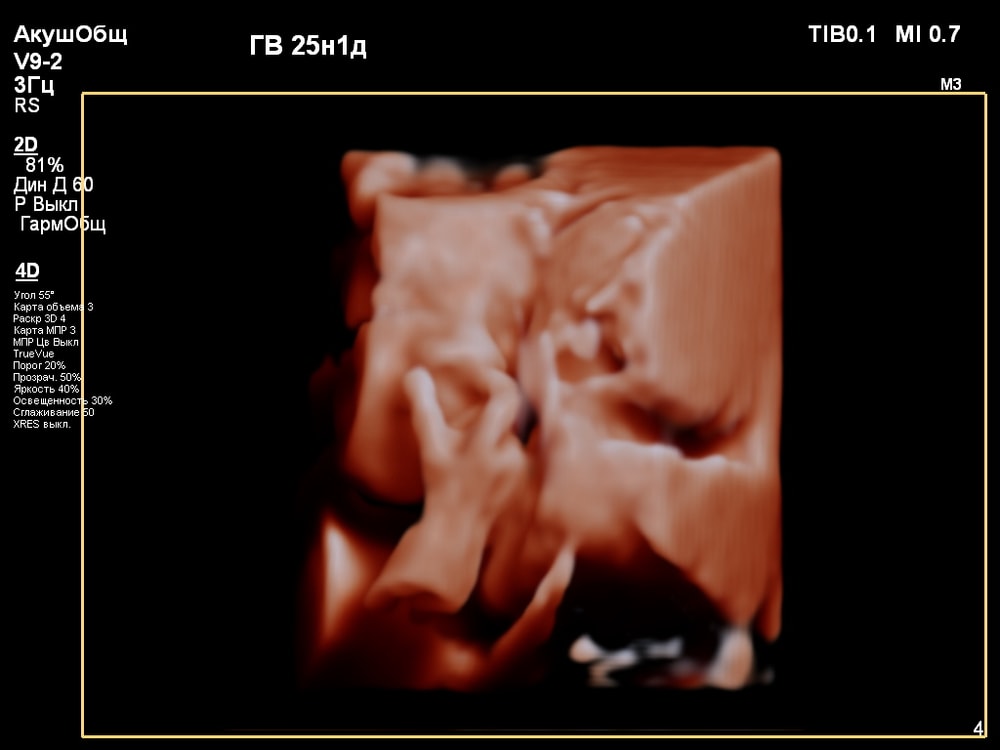

3D/4D УЗИ в 25 недель

УЗИ, КТГ, доплерПервая фотосессия малыша ещё в животике!😍 СНИМКИ С УЗИ👇

Когда переключили на 4D режим было сначала непонятно, что изображено на экране. Но врач всё показывала и обьясняла что на нём: где носик, губки, подбородок, что у личика ручки, малыш что-то жуёт, губками шевелит. Тогда картина начала вырисовываться и всё стало понятно, и в движении тоже)).

За 30 мин удалось увидеть многое (ребёночек не спал)! Он у меня в принципе парень активный, особенно лёжа на спине): на УЗИ, ещё в самом начале, малыш показал указательный палец и почесал им нос 😂, потом пытался большой палец засунуть в рот и пососать. Забавно было, когда он начал зевать и прикрывать ротик ладонью (воспитанный растёт). Ну и конечно, на радость родителям малыш улыбался🥰. Александра Евгеньевна смогла поймать все эти моменты и запечатлеть на снимке). Когда ребёночек закрывался, отворачивался - врач проводила общее 2D исследование, потом возвращалась к 4D.

😁😍🥹Я ИСПЫТАЛА НЕВЕРОЯТНУЮ РАДОСТЬ, ВОСТОРГ И УМИЛЕНИЕ)): впервые увидеть не абстрактные черно-белые тени, а узнаваемое личико своего ребенка, его движения – это мощнейший эмоциональный опыт, укрепляющий связь с малышом еще до рождения! Увидеть, как малыш активно двигается, зевает, сосет пальчик, улыбается – вызывает бурю положительных эмоций.

Иногда получить хорошую картинку сложно. Качество изображения сильно зависит от положения плода, количества околоплодных вод, расположения плаценты, толщины брюшной стенки. Мне в этом плане повезло, плацента была расположена по задней стенке матки, брюшная стенка у меня тоненькая, околоплодные воды в норме, малыш был в движении и можно было разглядеть его профиль.